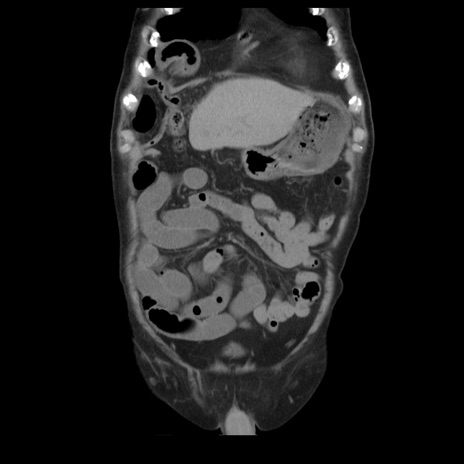

症例21(冠状断像)

【症例】70歳代男性

【主訴】腹痛

【現病歴】肝硬変・肝細胞癌にてかかりつけの方。約9時間前に食後より腹痛出現。症状が徐々に増悪し、嘔吐出現したため来院。

【既往歴】肝硬変、肝細胞癌(RFA、TACE後)

【身体所見】意識清明、表情苦悶様、BT 36℃、BP 129/78mmHg、P 88bpm、SpO2 97%(RA)、右上腹部から心窩部にかけて圧痛あり、反跳痛なし、筋性防御あり。

【データ】WBC 5800、CRP 0.16